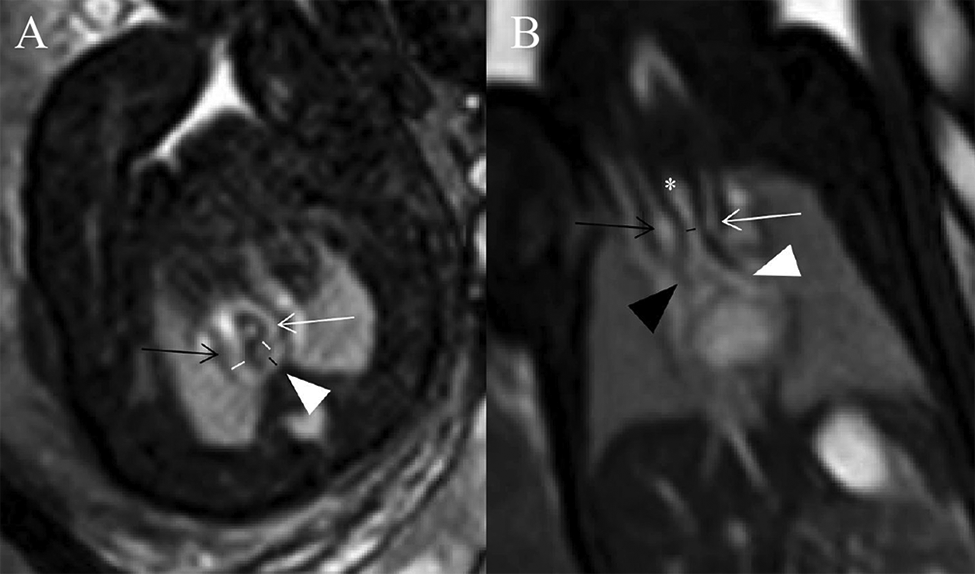

A structural anatomical assessment on fetal MRI was carried out retrospectively by two senior radiologists with 18 and 30 years of experience in pediatric MRI respectively (S-ZD and MZ). Fetal cardiovascular structures were analyzed using a modified anatomic segmental approach for CHD reported previously (5). The assessment of fetal cardiovascular structure mainly included the visceroatrial situs, position of the heart, position of the inferior vena cava and aorta relative to the midline, ventricular looping, ventriculo-arterial connections, aortic arch with branching, ductus arteriosus, trachea and esophagus, systemic and pulmonary venous connections, and intracardiac structures. A single pediatric radiologist with 3 years of experience in fetal cardiovascular MRI (XZ) measured the diameters of AoI and DA in all cases. The diameters of the AoI and DA were measured in the transverse view of AA before they entered into the descending aorta on SSFP imaging (8) (Figure 2A). All measurements were shown as the average of the two measurements. Congenital heart defects (CHDs) and extracardiac malformation and tracheal compression of all fetuses were recorded. The trachea was estimated from repetitive observations of the axial, coronal and sagittal planes. The diagnoses of tracheal compression were made based on a consensus between two radiologists (S-ZD and MZ). The tracheal diameters of fetuses with tracheal compression were measured in the coronal SSFP sequences views (showing the best configuration of the trachea) by another pediatric radiologist (XZ) (9) (Figure 2B).

Figure 2

(A,B) Diagrams of measuring the diameters of AoI, DA, and tracheal in a 29 weeks’ gestation fetus with DAA. (A) Measurements of AoI and DA diameter in the transverse view of AA. Fetal cardiovascular magnetic resonance SSFP sequence transverse view of AA image showed AoI (white lines) and DA (black line) diameter measured, right aortic arch (black open arrow), left aortic arch (white open arrow), left-sided DA (white arrowhead); (B) measurement of tracheal diameter on the coronal view. Fetal cardiovascular magnetic resonance SSFP sequence coronal view image showed the trachea (white asterisk), tracheal diameter measured (black line), right aortic arch (black open arrow), left aortic arch (white open arrow), right principal bronchus (black arrowhead), left principal bronchus (white arrowhead).